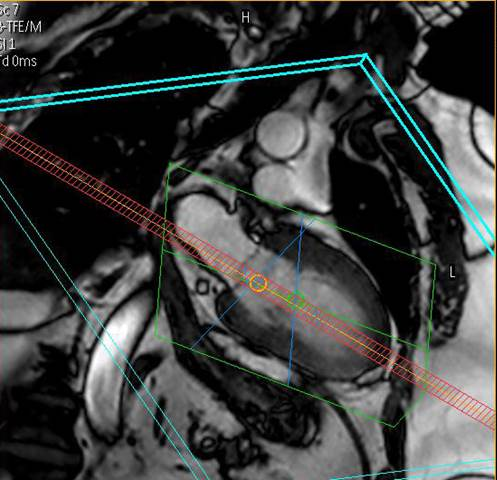

Wir bieten modernste MRT-Diagnostik.

Ganzkörper MR System - Philips healthcare